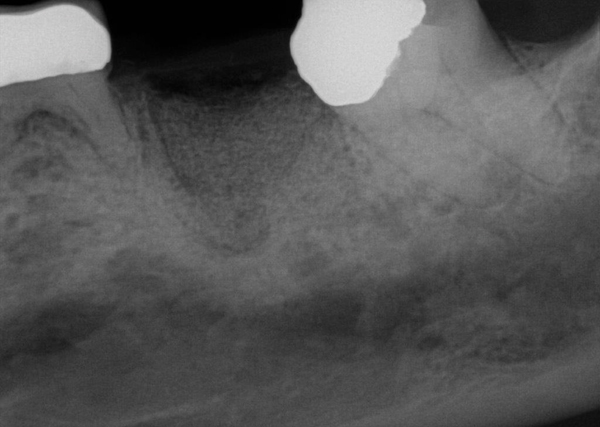

Fig 15. (Case 3) Radiograph of tooth No. 19, which had a hopeless prognosis.

Figure 15